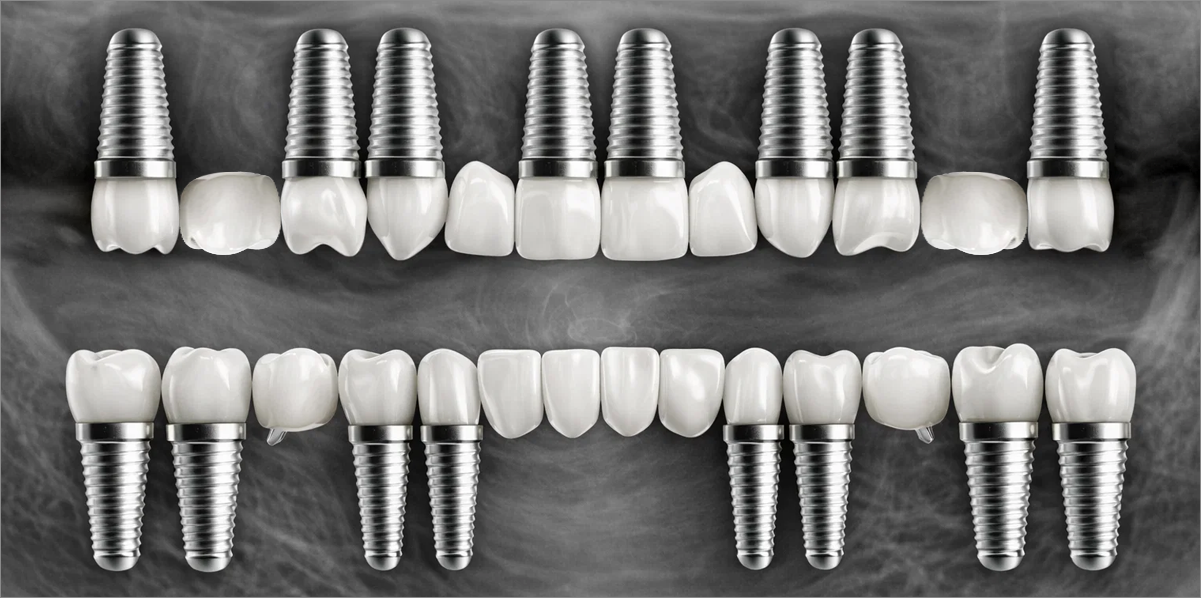

In full-mouth implant cases, implants are placed only where needed, and the remaining gaps are restored using a bridge (pontic) method — minimizing the total number of implants while achieving masticatory force comparable to natural teeth, helping to reduce the financial burden.

Bridge-type implant

Full-mouth implant restoration is categorized into full placement or minimal placement approaches.

• 01

Full Placement

Using a method of placing 8–9 implants in the maxilla and 8 implants in the mandible, this approach fully restores all 28 natural teeth, creating an oral environment most closely resembling

natural dentition.

• 02

Minimal Placement

Using a method of placing 6–7 implants in the maxilla and 6 in the mandible, this approach restores both posterior and anterior teeth, efficiently rehabilitating the entire oral cavity.